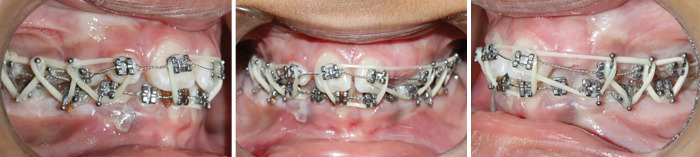

Case description: Three pediatric patients with mandibular fractures were treated using orthodontic appliances for IMF-case 1: a 9-year-old male with a left mandibular angle fracture was treated with stainless steel brackets and elastics for 2 weeks. Follow-up showed full recovery with no pain or occlusal issues. Case 2: a 6-year-old male with bilateral condylar and symphyseal fractures was treated with brackets on all teeth up to the deciduous second molars. After 2 weeks, improved occlusion and mouth opening were noted. Case 3: a 6-year-old female with a right condylar fracture showed improved occlusion and symptom resolution after 2 weeks of treatment.